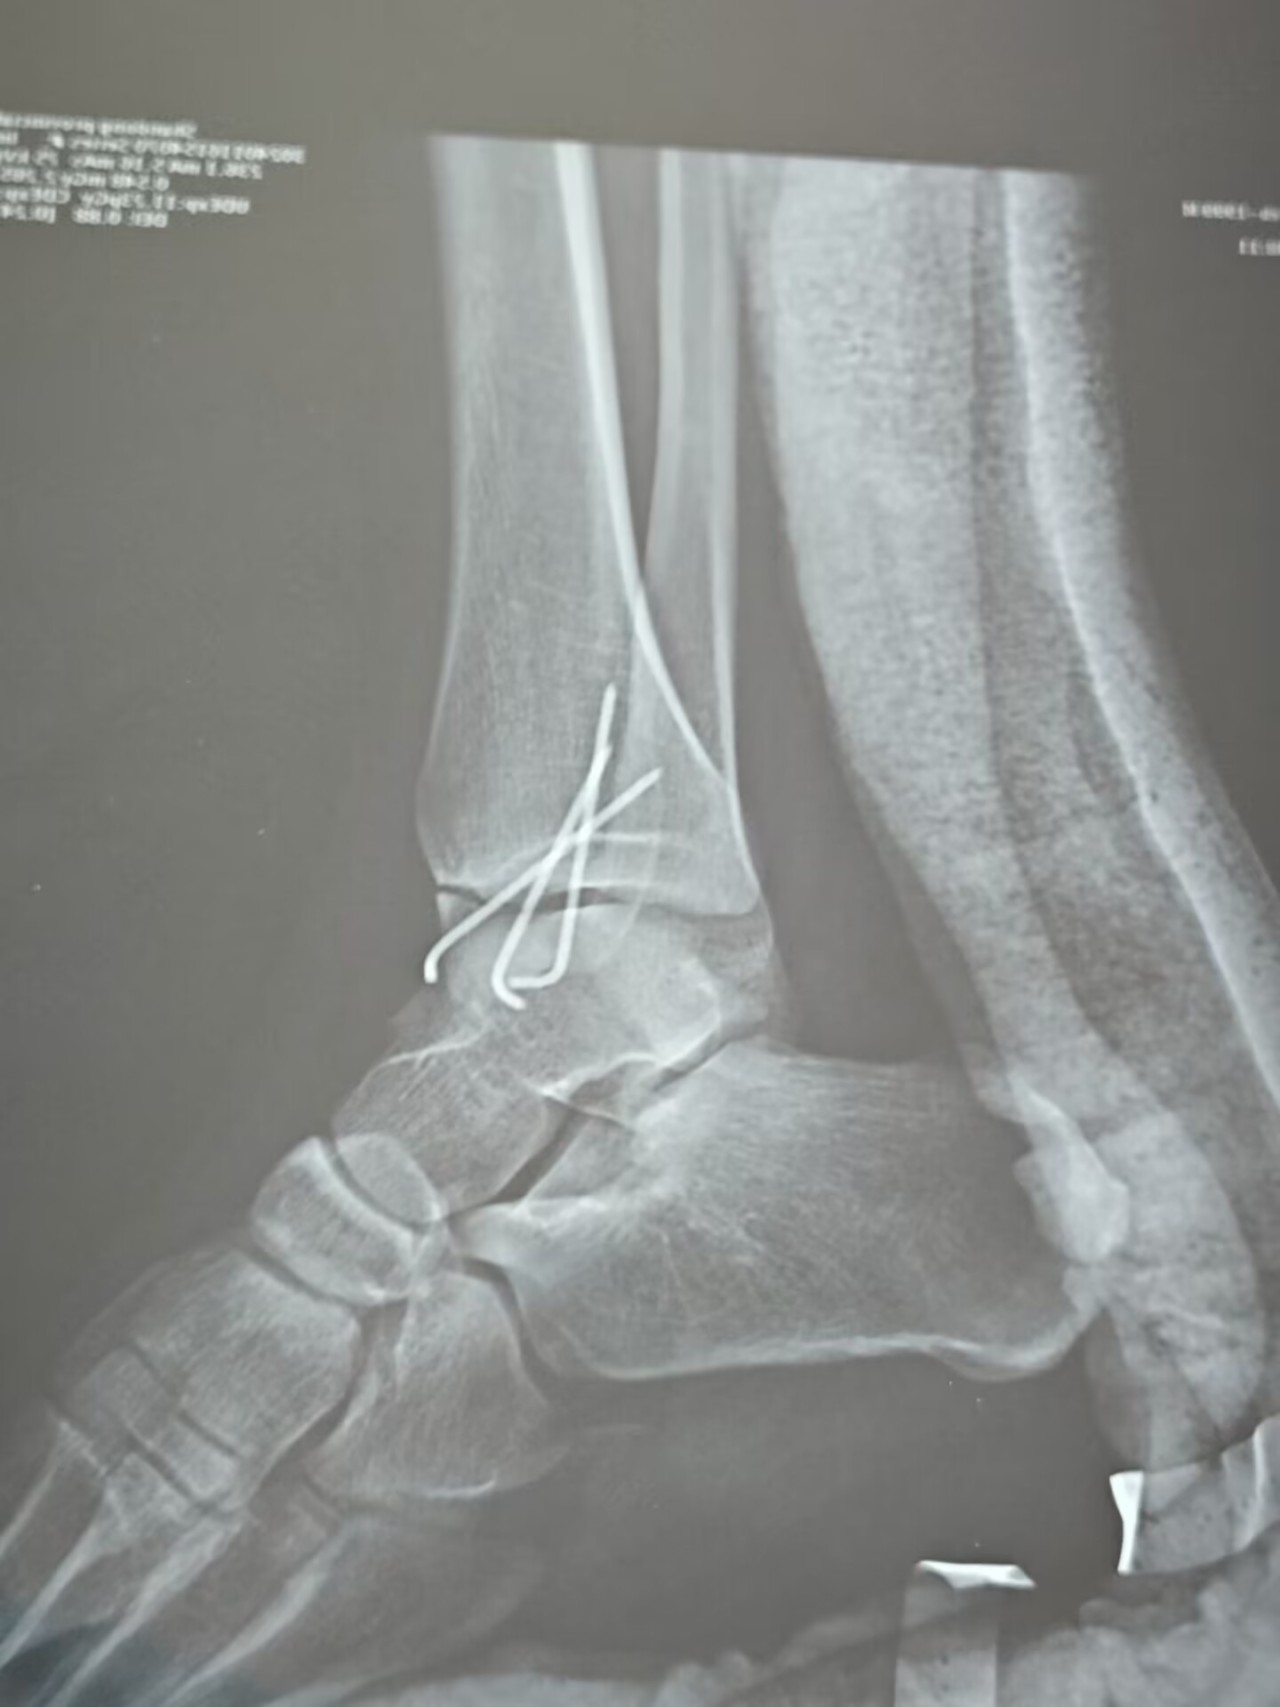

![]()

鋼釘

骨科的手術還是非常的簡單,給我的感覺就是拿着電鋸和錘子改造我的身體(快進到擁有賽博義肢),在麻醉的作用下,醫生擺弄我的腿我也沒有什麼知覺,很快就是呼呼睡過去,再醒來的時候我已經擁有了一個非常沉重且熱乎的新鮮石膏。